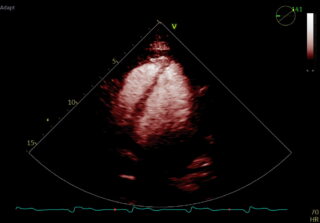

Kontrastowa echokardiografia wysiłkowa z oceną perfuzji mięśnia sercowego to zaawansowane, nieinwazyjne badanie kardiologiczne, które umożliwia ciągłe obrazowanie serca przez cały czas trwania wysiłku oraz jednoczesną ocenę kurczliwości, perfuzji i odpowiedzi hemodynamicznej.

Badanie wykonywane jest podczas kontrolowanego wysiłku fizycznego na ergometrze leżankowym, co pozwala na stabilne i nieprzerwane obrazowanie echokardiograficzne w czasie rzeczywistym, również na kolejnych, narastających stopniach obciążenia.

- ✔ poprawia jakość obrazowania jam i ścian serca,

- ✔ umożliwia bezpośrednią ocenę perfuzji mięśnia sercowego,

- ✔ znacząco zwiększa czułość wykrywania niedokrwienia, także we wczesnej fazie wysiłku.